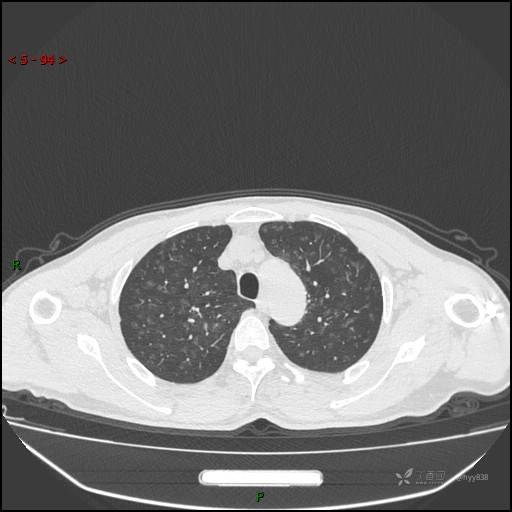

呼吸科电话会诊病例:过敏性肺炎 VS 吸烟相关间质性肺炎 VS 尘肺……结果公布~

性别:男

年龄:55岁

简要病史:渐进性呼吸困难。

胸部CT平扫

电焊工尘肺 (2)